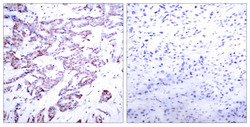

Immunohistochemistry

STJ90415 IHC